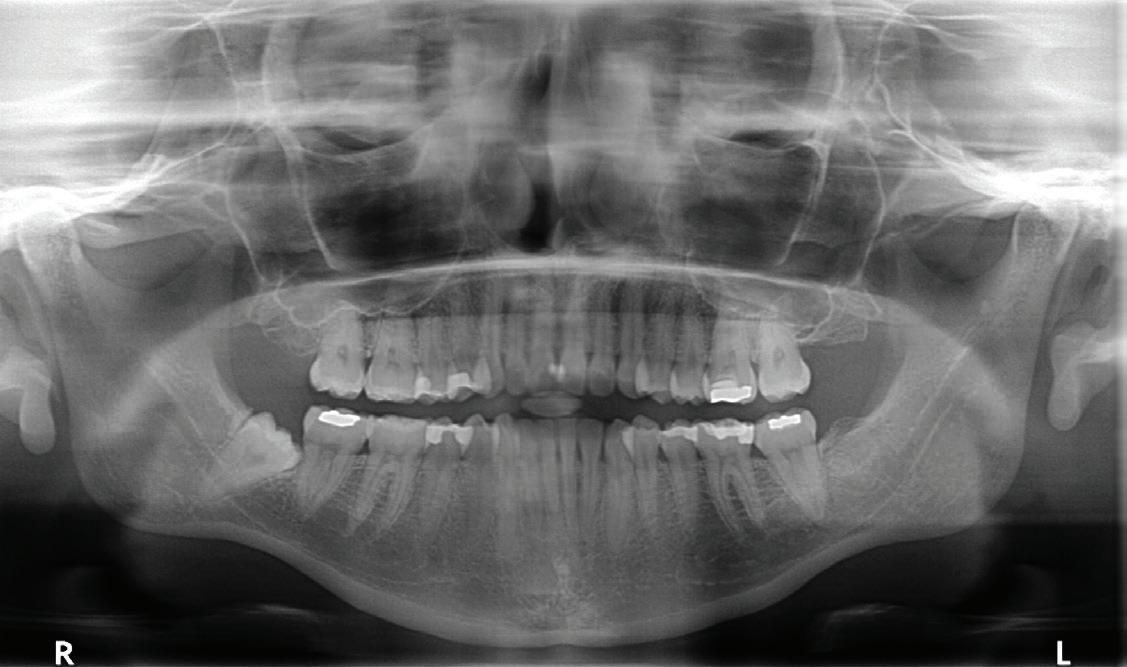

Coronectomy isn’t usually recommended if the tooth or root is infected or in younger patients whose roots aren’t yet fully developed. Dr. Pogrel and his colleagues also found that “teeth that are horizontally impacted along the course of the [IAN] may be unsuitable for this technique because sectioning of the tooth itself could endanger the nerve.” But for other patients, coronectomy is indicated if a panoramic plain-film X-ray (often followed by a confirming cone-beam computed tomography) shows that a root’s proximity to the IAN poses a danger of nerve damage.

Oral surgeon Rosie Noordhoek, DDS, says that there are some definite signs on panoramic X-rays that indicate a higher risk of sensory nerve damage: “when the root gets darker, for instance, or the nerve is displaced, or you can’t see the whole nerve canal.” To confirm that coronectomy is the preferable course, says Dr. Noordhoek, “we usually recommend a CBCT at that point.”

7 Radiographic Signs By Rood And Shehab

Source: Appl Sci . 2021, 11(2), 816; https://doi.org/10.3390/app11020816